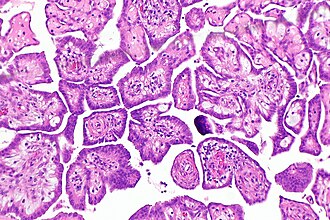

In pathology, papillary refers to a nipple-like projection with a fibrovascular core.

Histologic definition - papilla:

- Nipple-shaped structure consisting of epithelium on a fibrovascular core.

- Fibrovascular core = fibrous tissue + least one blood vessel.

- Micropapilla - nipple-shaped structure without blood vessels; usually smaller than papillae.

- Pseudopapilla - cells distant from the blood vessels undergo necrosis imparting a papillary-like appearance, e.g. solid pseudopapillary tumour.